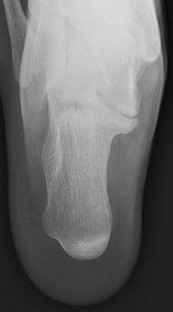

QUESTION 7

Figures 7a through 7h

1

Normal foot

2

Calcaneonavicular (CN) coalition

3

Talocalcaneal (TC) middle facet coalition

4

TC posterior facet coalition

Figure 7a shows a mild flatfoot with lateral peritalar subluxation of the navicular. Figure 7b does not show an open MF and has a questionable C sign. Figure 7c shows that the opening between the calcaneus and the navicular appears normal without distortion. Figures 7d, 7e, 7g, and 7h show a lateral sloping distorted middle facet consistent with a middle facet coalition, and Figure 7f shows a normal posterior facet.